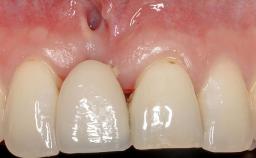

Implant Placement in the Esthetic Zone and Coverage of Multiple Gingival Recessions

This case illustrates use of a modified ‘tunnel’ technique, which has been shown to be highly effective in root coverage procedures. The tunnel technique is used to achieve soft-tissue augmentation across the anterior area, including the planned implant site, using collagen matrix as grafting material. The patient is a 47-year-old woman with high esthetic expectations. Her main concern was the appearance of the anterior teeth and their “elongation”.

Soft Tissue Contour and Volume Significantly deficient